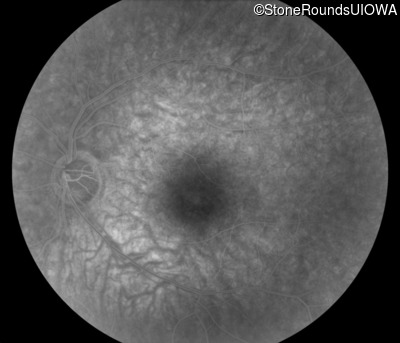

Infrared Fundus Photograph - Right - 20/20 -1

Exemplar